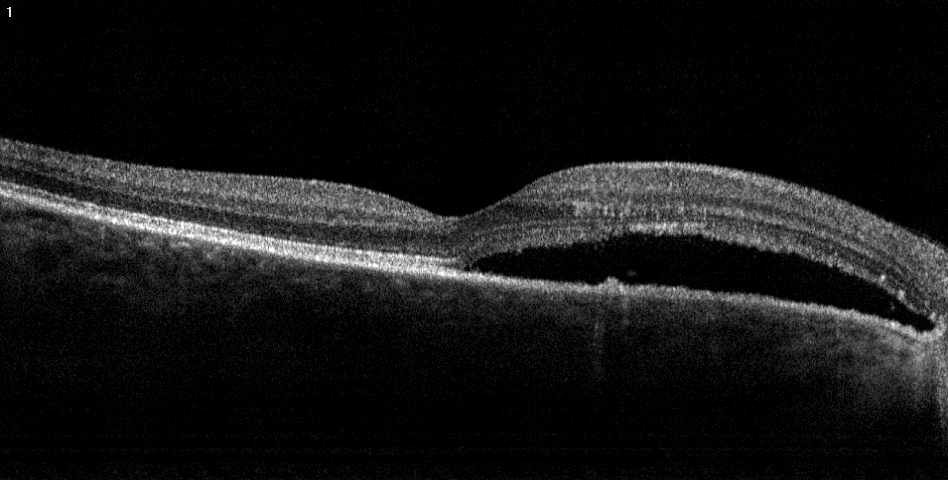

The hallmark of this disease is the development of fluid under the retina, in the so-called subretinal space. Various metabolic processes lead to an increase of pressure and subsequently, to the development of a small hole in the lowest layer of the retina, the pigment epithelium. As a result, fluid then enters the subretinal space. Common complaints are grey spots in the center of vision and sometimes lines that are bent or curved instead of being straight.